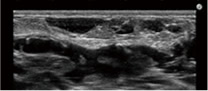

- 事前のエコー検査で異常の有無を確認

- エコー検査で脂肪の定着をチェック